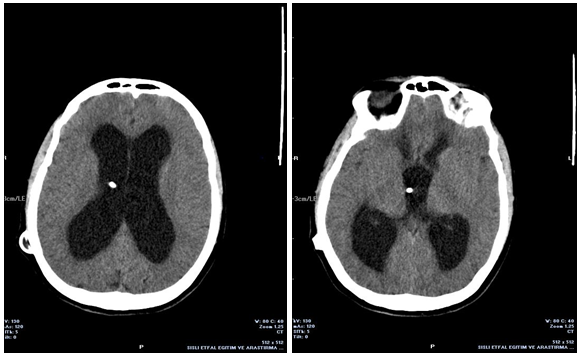

A 29 year-old woman gravida 3 para 0, abortion 2, who was at 37 weeks of gestation, was admitted to the neurosurgery clinic of our hospital with a complaint of headache, dizziness, urinary and fecal incontinence. Her history showed complaints of gait imbalance and a headache for the past 3 months. Recently in the last month she developed urinary and fecal incontinence. Her neurological examination revealed a loss of balance and a loss of anal and urinary sphincter tones. A cranial CT scan showed dilatation of both the lateral ventricles and the third ventricle (Figure 1). The patient was diagnosed with a VP shunt dysfunction. She had a ventriculoperitoneal shunt placed 3 years ago for idiopathic hydrocephalus treatment. She had an approval from her neurosurgeon prior to her pregnancy. After her complaints, she was referred to our department. On the obstetrical ultrasonography, fetal biometric measurements were consistent with the 37 weeks of gestation. The amniotic fluid index was normal and no placental pathology was observed. Due to her rapid deteriorating neurological status, cesarean section under spinal anesthesia was planned with the recommendation of neurosurgeons. During the operation the abdominal section of the shunt was observed observed in appropriate localization. A healthy male infant weighing 3240g was delivered with an APGAR of 8 at 1 minute. Antibiotic prophylaxis was started after the delivery using 2 doses of cephalosporine during the first 24 hours. No postnatal and postpartum complications were observed. The VP shunt may be compressed by the gravid uterus and this may result in decreased cerebrospinal fluid flow through the shunt and increased intracranial pressure. So that, after the operation her neurological status improved quickly. On fourth postoperative day a neurosurgical examination showed no need for surgical intervention for the shunt. The patient was discharged from hospital on the seventh day without complications.

Figure 1 Cranial CT scan showed dilatation of both the lateral ventricles and the third ventricle and the presence of the ventriculoperitoneal shunt.